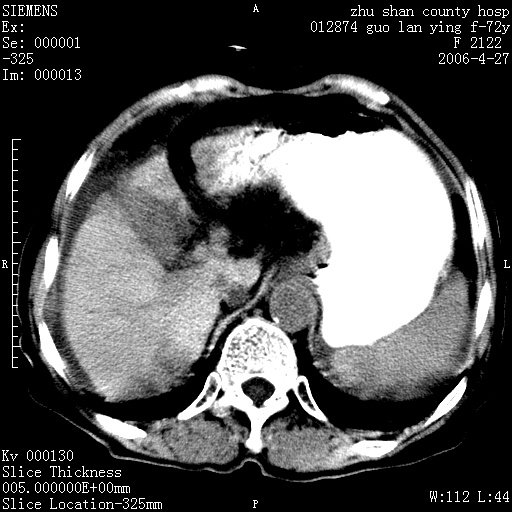

病人 女性 72岁 b超要求ct检查!

平扫所见:胆囊区两点壮高密度影,灶周有伪影{请问楼主患者有手术病史?}。肝实质内未见明显异常{建议强化或mri}.腹腔有少量积液,脾明显增大.右肾形态似不规则?

腹腔内示积液征,脾脏略增大,肝脏由于运动伪影较多,影响观察,内未见明显高密度区,胆囊内示两处高密度结石。胃窦部壁轻度增厚。另外,肝脏的前缘似有游历气体。不知病人的临床如何?有必要做胃的检查,还有,看看骨窗是否有腹腔游离气体还是肠管影响的。

如果b超对肝脏有怀疑,肝脏的增强扫描还是尽量去做。

肝脏缩小,脾脏增大,肝脾外缘及胆囊窝液性密度影,肝脾ct值正常,胆囊区见两个类圆形高密度影,下腔静脉前方类圆形软组织密度影为肝脏岛叶,胃幽门区见软组织密度影,十二指肠钡剂充盈不好.

1:腹水2:胆囊结石3肝硬化?(不确定,请结合临床)4幽门区占位?(建议胃肠透视)

肝硬化,脾大,少量腹水

肝硬化、脾肿大,腹水,胆囊区高密度影(结石或异物),是否有外伤史

肝硬化、腹水、脾大,胆囊结石可以肯定。只是肝右叶两个低密度有必要增强确定一下;排除小肝癌。

谢谢牟教授在百忙之中还认真的点评我的帖子!也谢谢大家的鼎力相助,此病人是我们医院护理部主任的母亲!病人以前无特别不舒适!昨天b超后发现有问题!做ct的目的在于排除肝内占位性病变,此病人以前无手术外伤史.